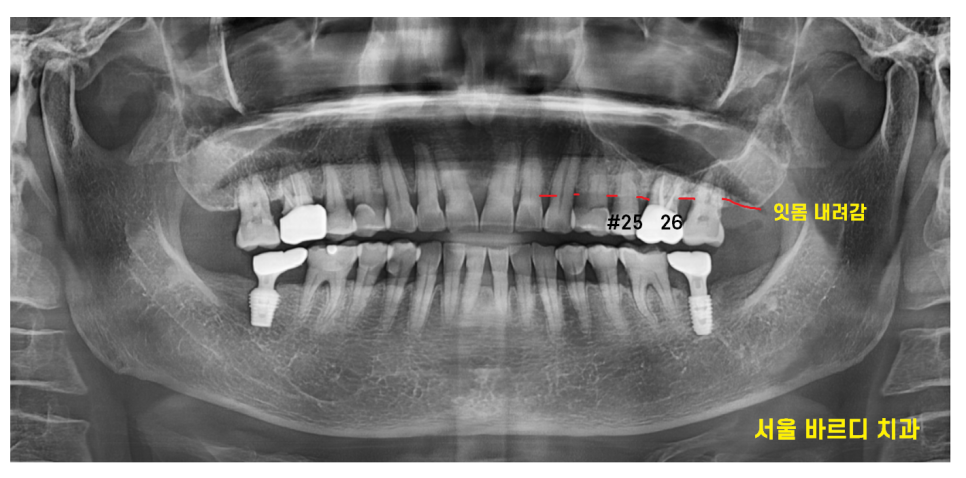

x-ray 먼저 촬영해 보니

잇몸이 전반적으로 내려간 풍치가 발견되었습니다.

임플란트를 위해 ct 촬영을 시행했습니다.